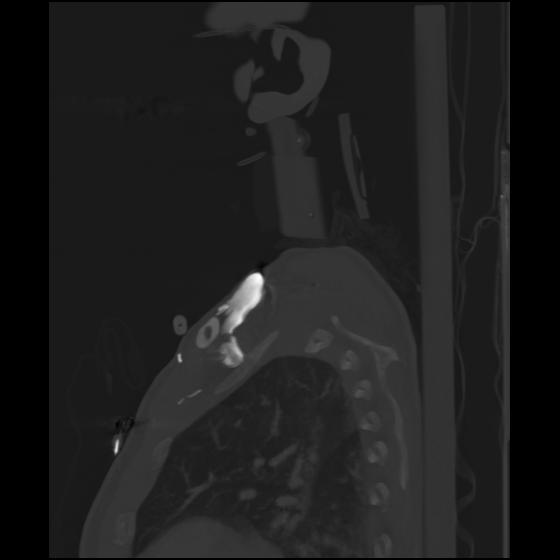

24 ANGIO,CE,Sag-MIP,5.000,ANGIO,Sag-MIP,